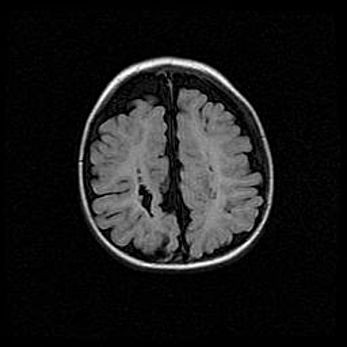

Ниже представлена  галерея МРТ снимков, полученных с применением LMT неонатальных матричных РЧ катушек. Также каждая группа МРТ снимков сопровождается информацией о пациенте (диагноз, возраст, вес, пол, срок гестации) и краткой сопроводительной расшифровкой диагноза.

Церебральная ишемия II.

Возраст: 5 дней

Вес: 3400 г

Пол: женский

Окружность головы: 35 см

Срок гестации: 39 недель

Церебральная ишемия – это заболевание, характеризующееся недостаточностью (гипоксией) либо полным прекращением (аноксией) снабжения мозга кислородом по причине закупорки одного или нескольких сосудов. Это приводит к  что метаболическим расстройствам различной степени тяжести в тканях головного мозга, развитию коагуляционных некрозов и гибели нейронов.